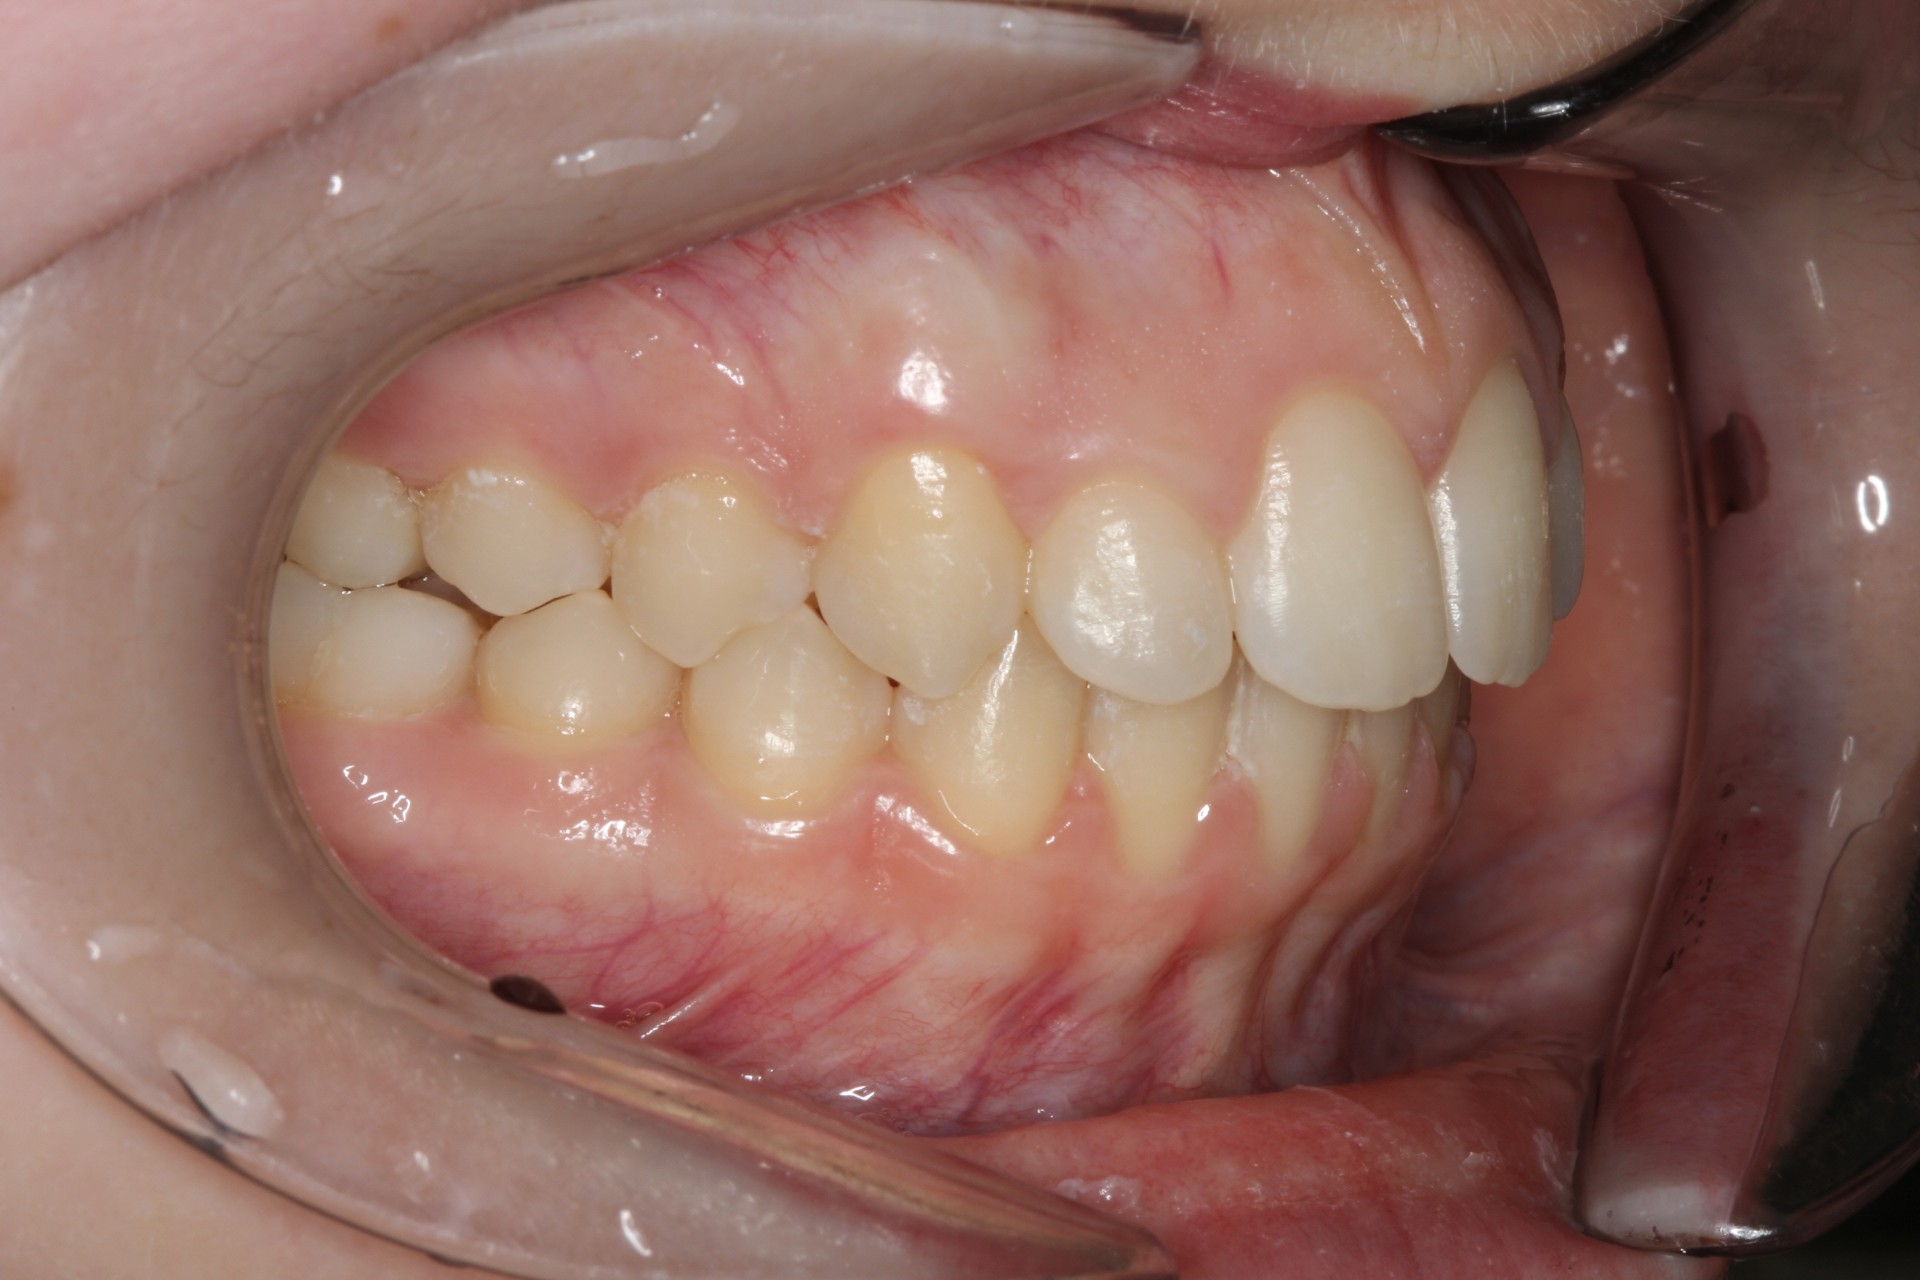

Crowding with lateral open bite – Child case